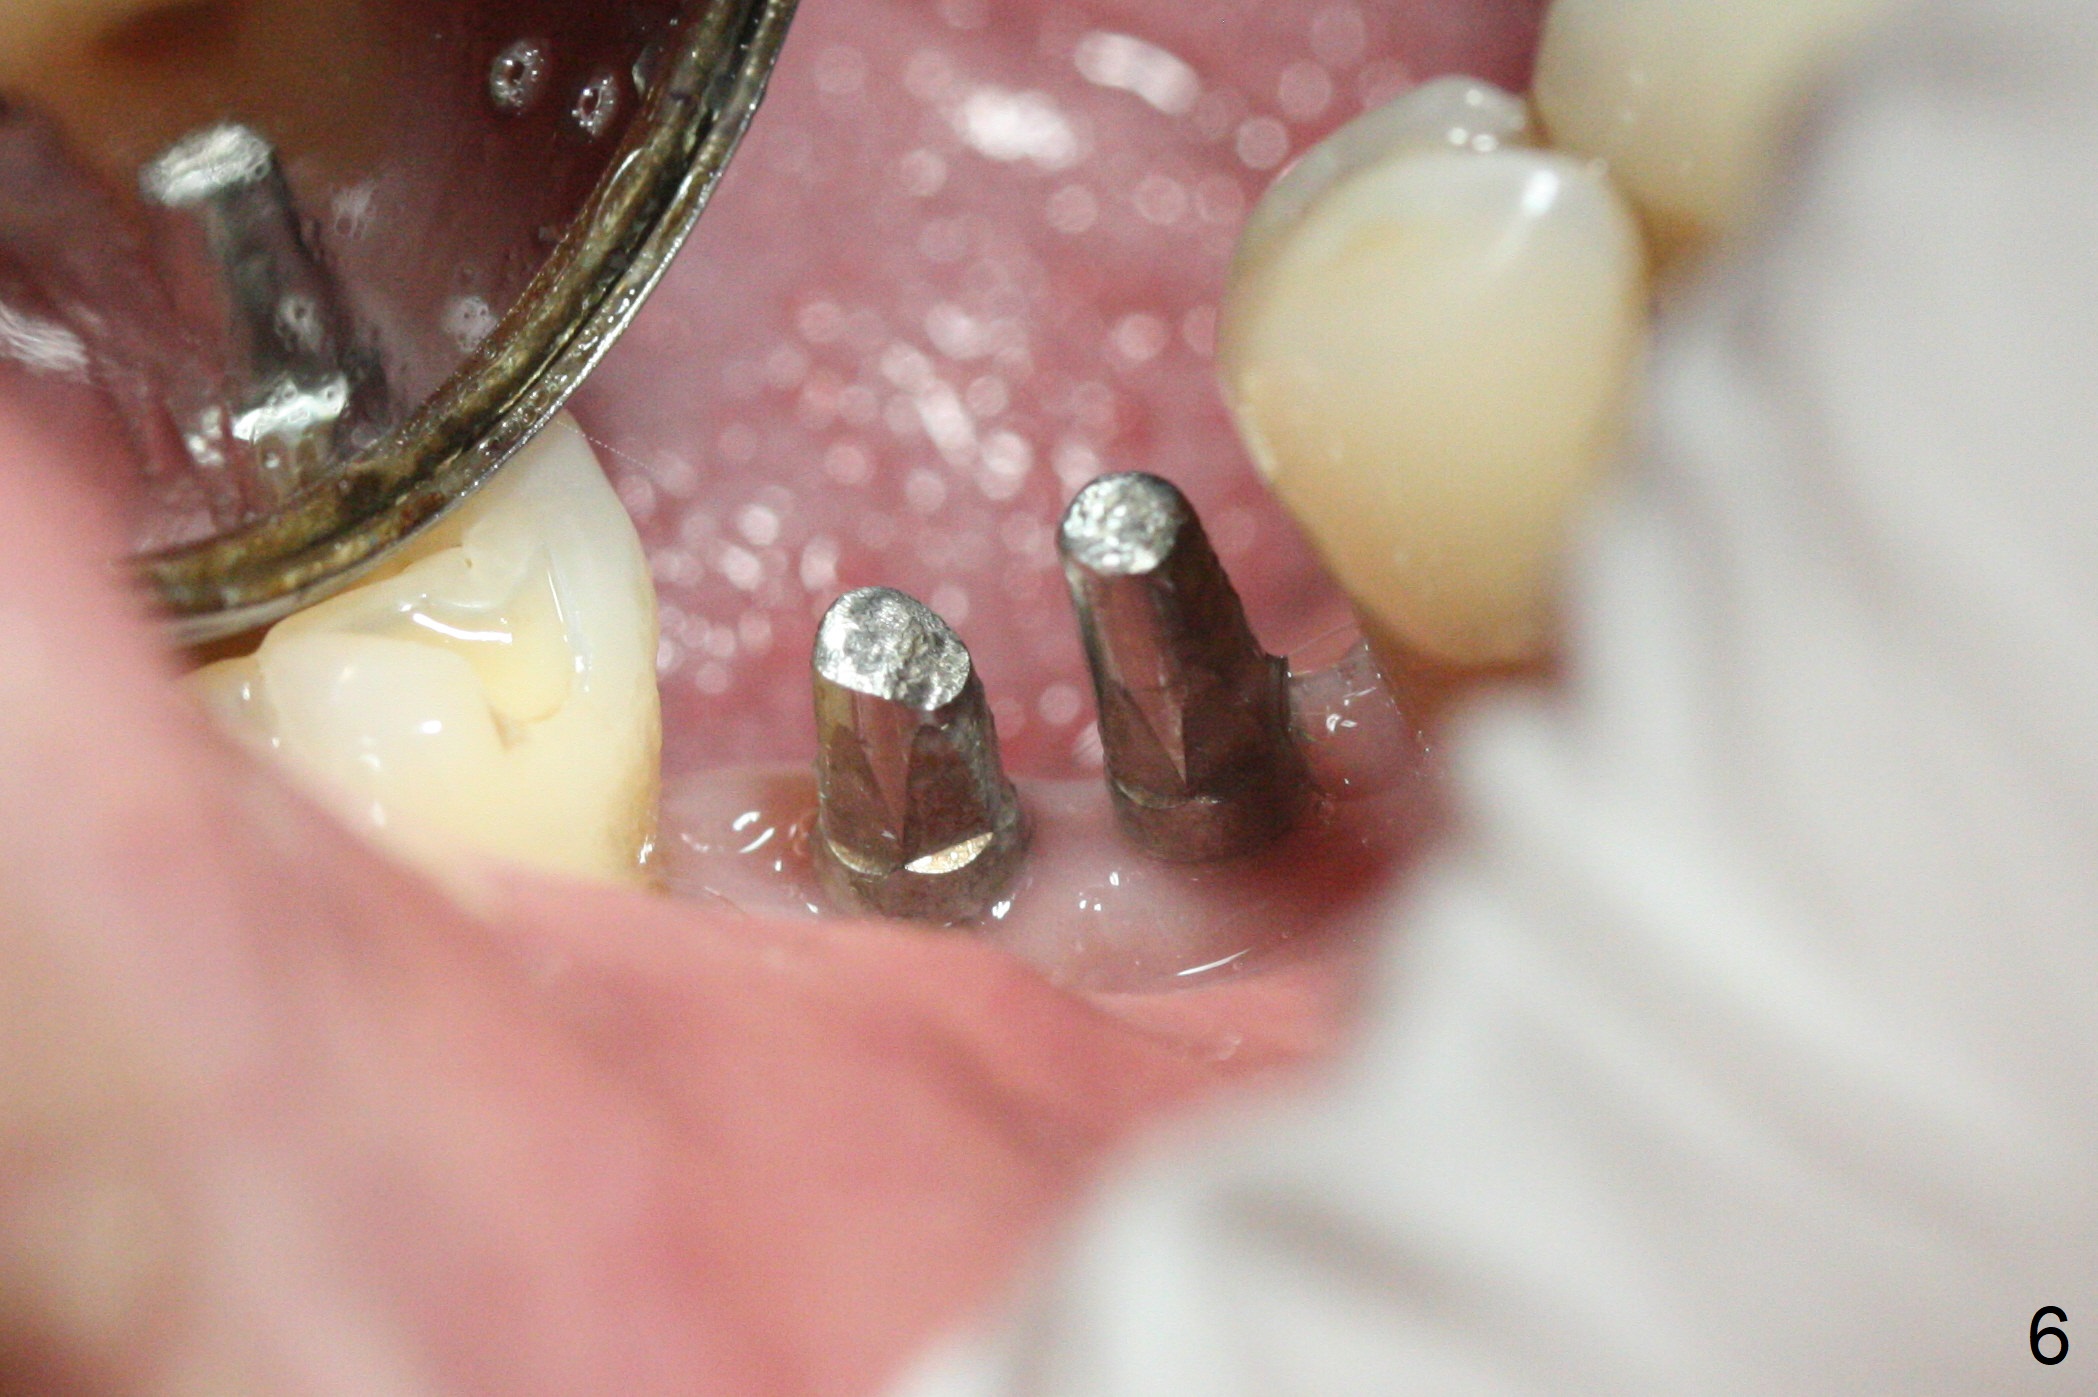

The wide mesiodistal space at #29 is most likely due to congenital missing permanent tooth (i.e., deciduous molar retention before extraction 34 years ago). The patient is now 62 years old. In fact the buccolingual width is not so narrow (Fig.1). After incision, the ridge is approximately 5 mm. Two osteotomies are established with 1.2 mm drill at 8 mm mesially and 1.5 mm one at 10 mm distally (Fig.2). The apparent approximation of the mesial osteotomy to the Mental Loop (red dashed line) is related to X-ray angulation, since there is 1-2 mm separation when two of 2x10(2) mm 1-piece implants are placed (Fig.3,4). Insertion torques of the mesial and distal implants are less than 25 and 15 Ncm, respectively. In fact bone graft is placed around the distolingual root of the tooth #30 after calculus removal (Fig.4 <). Following reduction of the abutments, periodontal dressing is applied locally. The dressing dislodged 13 days postop (Fig.5). A provisional is going to be fabricated 4 weeks postop when the wound heals (Fig.6). No bone loss is observed 4 months postop (Fig.7).